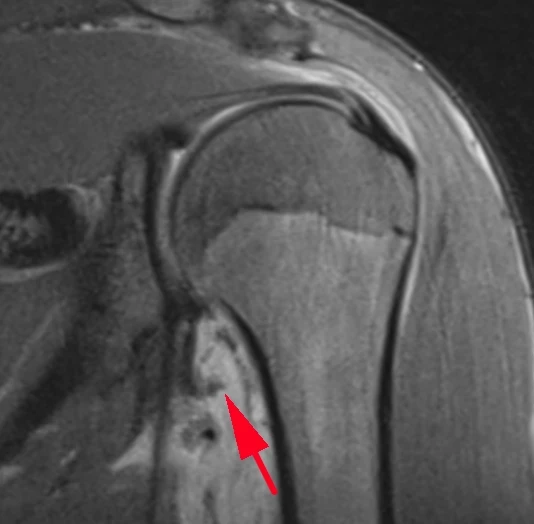

А вот вдогонку ещё костное повреждение Банкарта, парень 20 лет. Последствия переднего вывиха плеча.

Из-за отрыва сухожилия подлопаточной мышцы вывихнулось медиально сухожилие длинной головки бицепса. Сухожилие подлопаточной мышцы является одновременно удерживателем длинной головки бицепса в межбугорковой борозде, вплетаясь в малый бугорок плеча и как бы продолжаясь в поперечную связку (связку Броди), которую некоторые считают не истинной связкой, а частью сухожилия надостной мышцы.